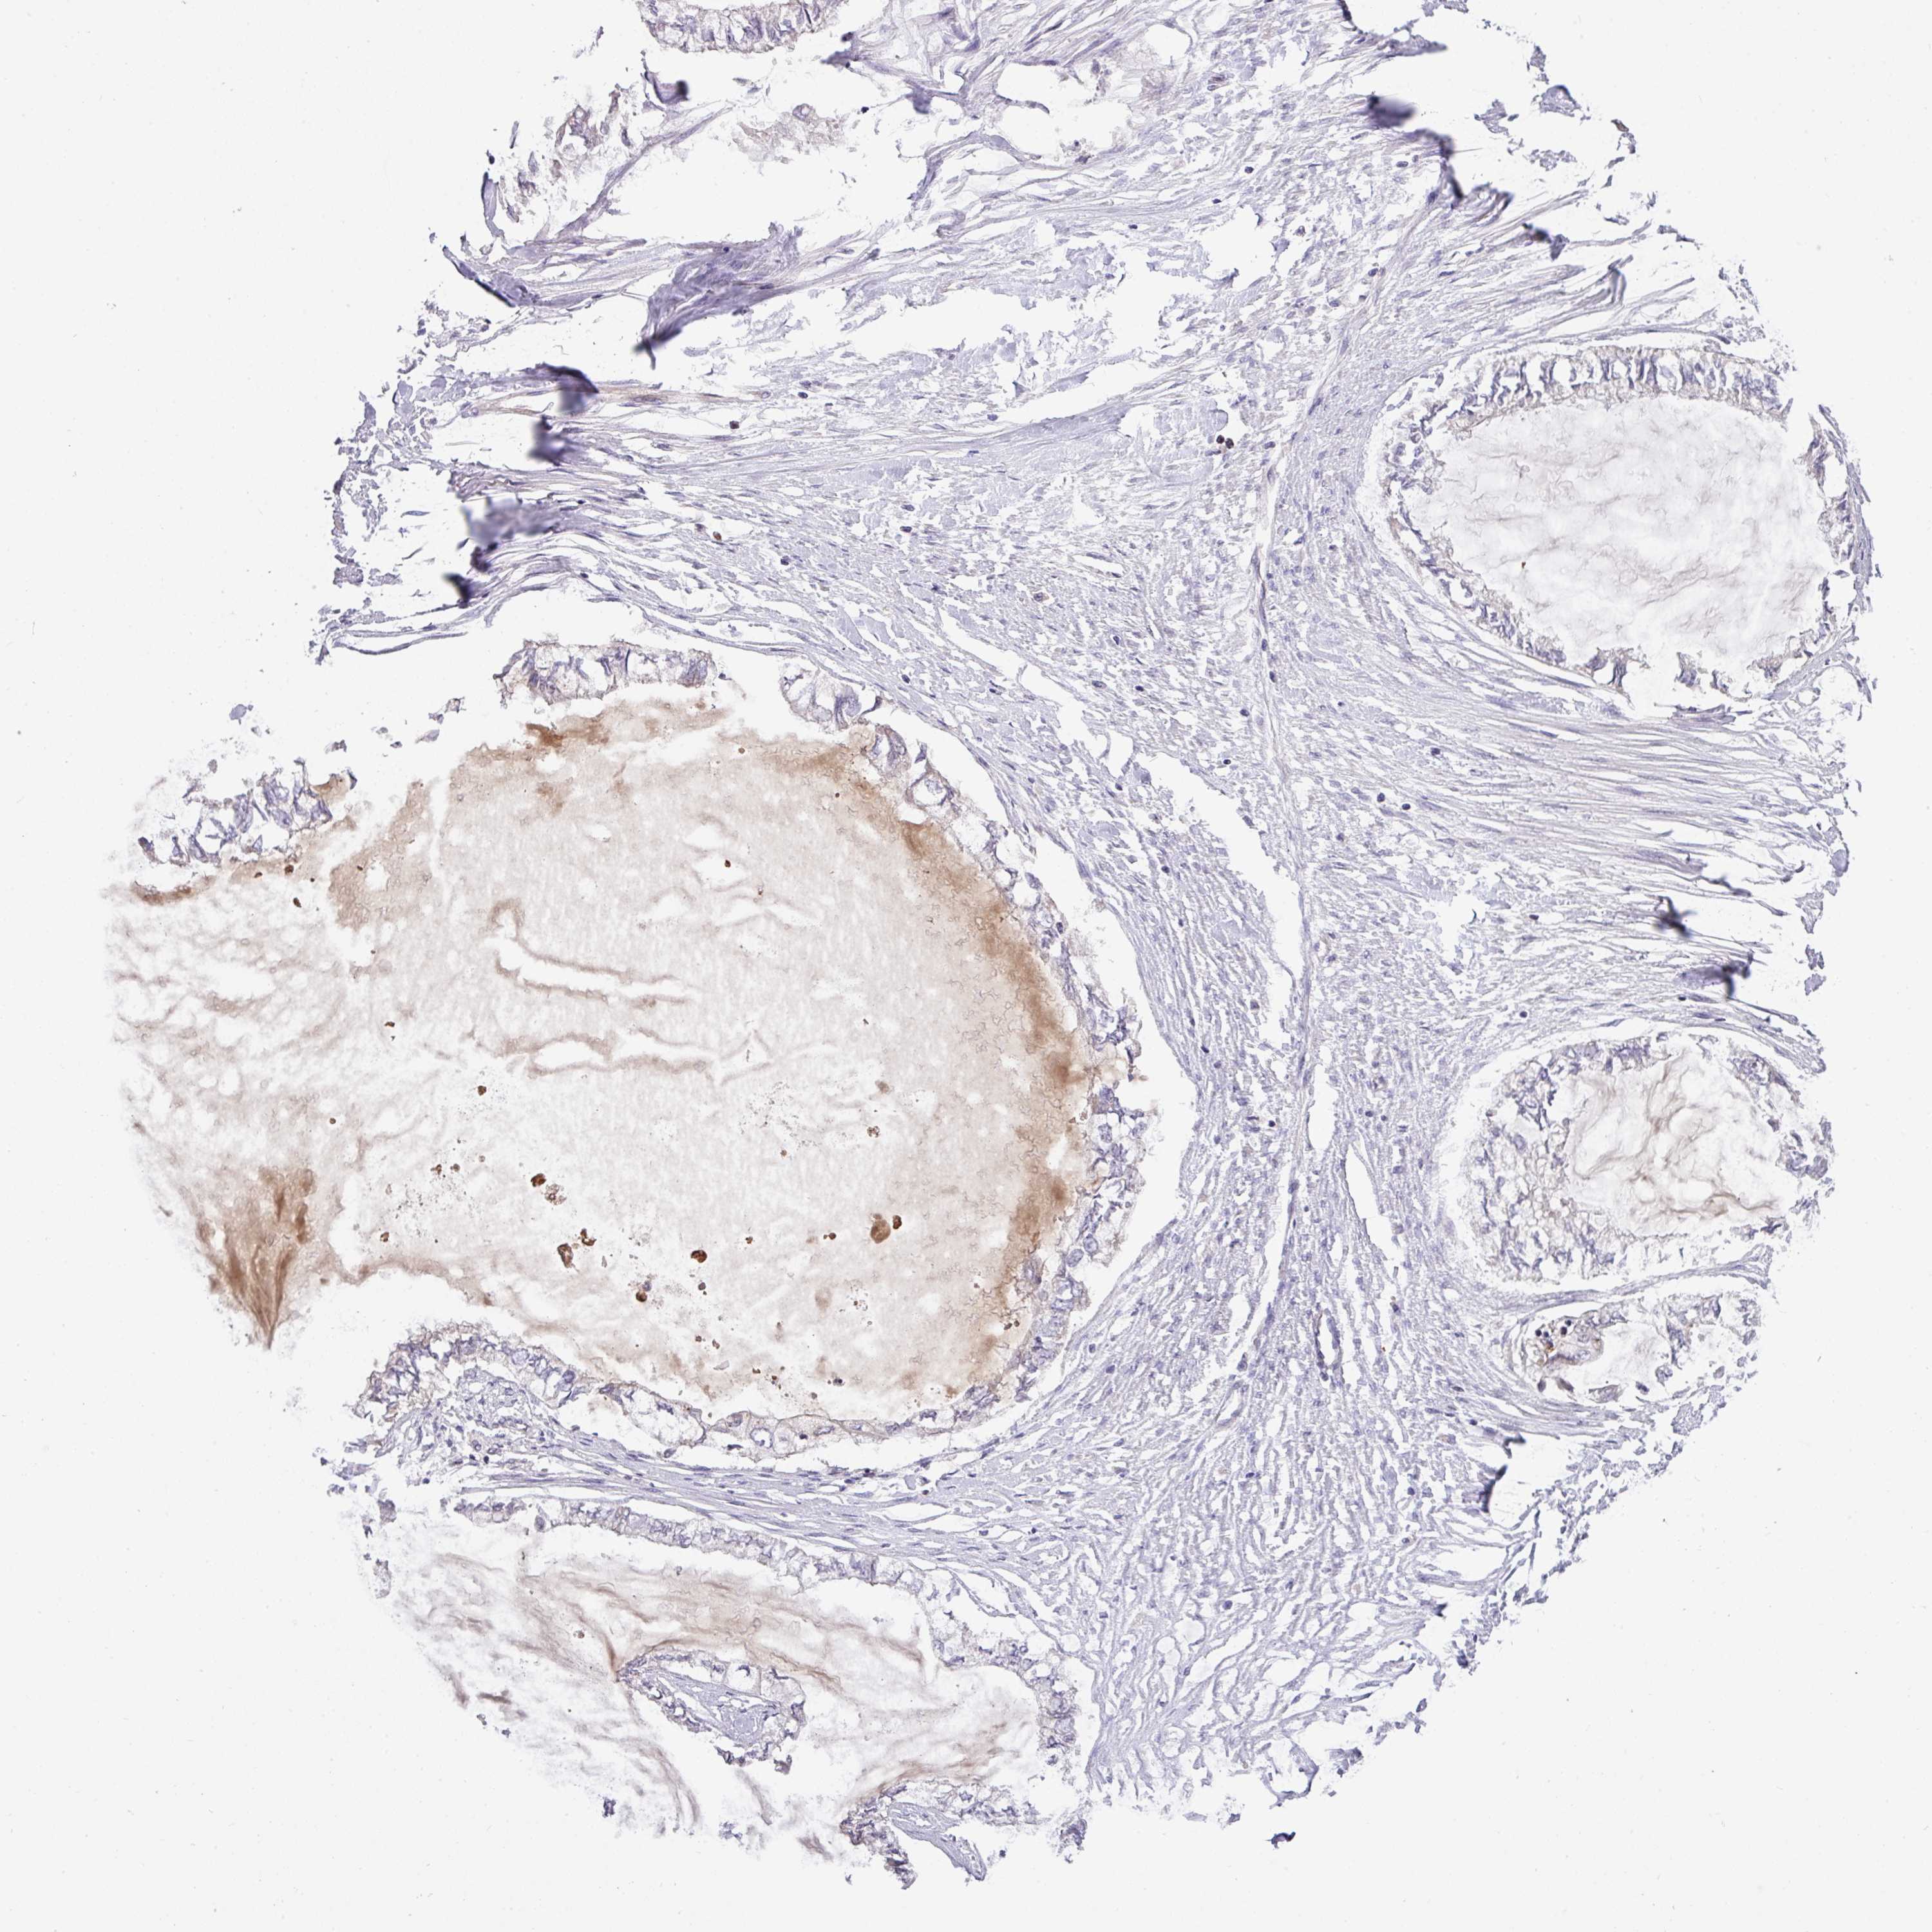

OVARIAN CANCER - Protein expressioni

A mouse-over function shows sample information and annotation data. Click on an image to view it in a full screen mode. Samples can be filtered based on level of antibody staining by selecting one or several of the following categories: high, medium, low and not detected. The assay and annotation is described here.

Note that samples used for immunohistochemistry by the Human Protein Atlas do not correspond to samples in the TCGA dataset.

Antibody stainingi

Antibody staining in the annotated cell types in the current human tissue is reported as not detected, low, medium, or high, based on conventional immunohistochemistry profiling in selected tissues. This score is based on the combination of the staining intensity and fraction of stained cells.

Each image is clickable and will lead to virtual microscopy that enables deeper exploration of all samples and also displays staining intensity scores, fraction scores and subcellular localization as well as patient and tissue information for each sample.

Antibody HPA051421

Antibody HPA054639

Staining

High

Medium

Low

Not detected

Intensity

Strong

Moderate

Weak

Negative

Quantity

>75%

75%-25%

<25%

None

Location

Nuclear

Cytoplasmic/membranous

Cytoplasmic/membranous,nuclear

Cystadenocarcinoma, serous, NOS

Cystadenocarcinoma, mucinous, NOS

Adenocarcinoma, NOS

Carcinoma, endometroid